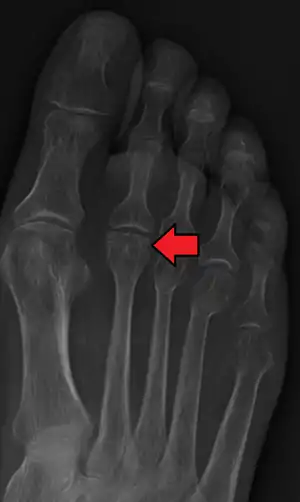

![]() | |

| Freiberg disease as seen on plain film | |